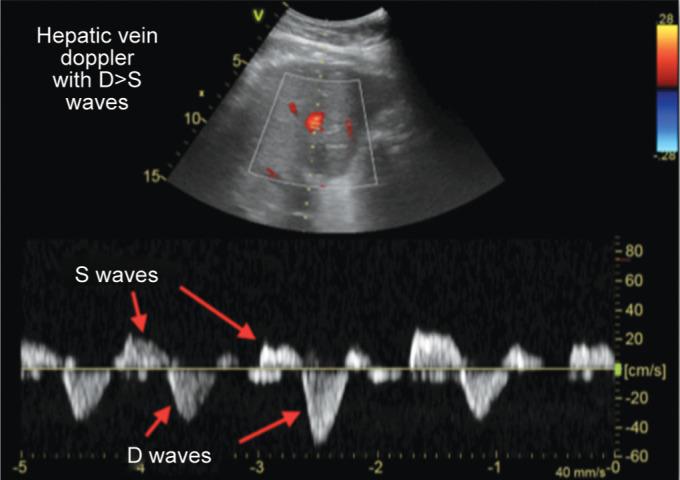

Patients above 18 years admitted in ICU with a provisional diagnosis of cardiorenal syndrome were included in the study. Those with inadequate window, inferior vena cava (IVC) thrombus, and known case of cirrhosis with portal hypertension were excluded from the study. Patients underwent ultrasound examination with serial determination till AKI resolved or patient is initiated on dialysis. Venous excess ultrasound score (VEXUS) comprising inferior vena cava, hepatic vein waveform, and portal vein pulsatility was assessed.

Thirty patients were enrolled for the study. The mean age was 59.53 ± 16.47 with 21 (70%) males. Mean sequential organ failure assessment (SOFA) score was 5.03 ± 1.97. Fourteen patients (46.7%) were in AKI stage 1, while eight patients (26.7%) were in AKI stage 2 and stage 3 each. Twenty patients (66.7%) had VEXUS grade III. Resolution of AKI injury showed significant correlation with improvement in VEXUS grade ( value 0.003). Similarly, there was significant association between changes in VEXUS grade and fluid balance ( value 0.006). There was no correlation between central venous pressure (CVP), left ventricular function, and right ventricular function with change in VEXUS grade.

The study shows that a combined grading of IVC, hepatic vein, and portal vein might reliably demonstrate venous congestion and aid in the clinical decision to perform fluid removal.